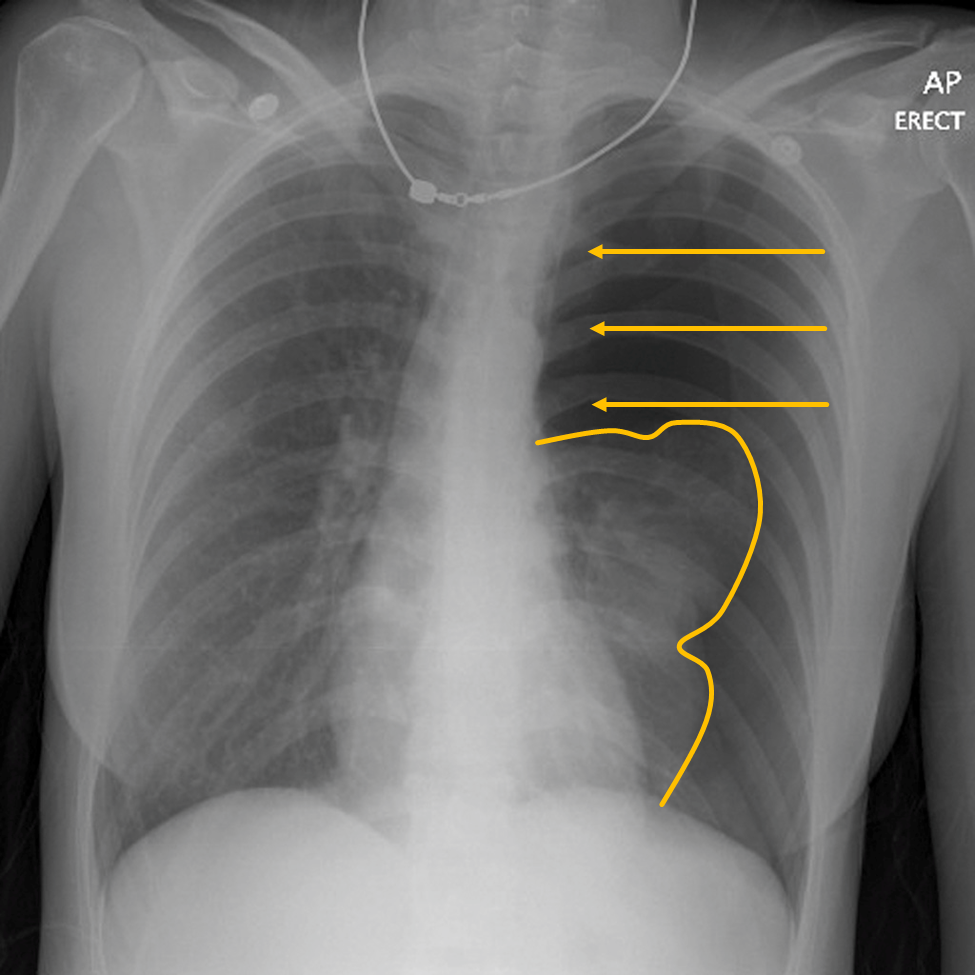

What is this abnormality

Pneumothorax

What is a pneumothorax

3 types/causes of pneumothorax

In some cases, intra-pleural air volume will increase, exerting pressure on the mediastinal and intra-thoracic structures.

What is the name of this medical emergency?

Tension Pneumothorax